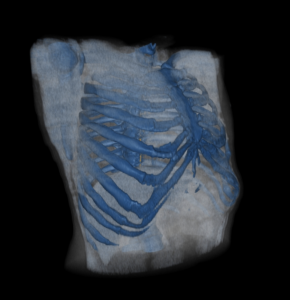

With rib 10 now considered standard treatment, the next logical and evolving question is whether rib 9 can also be addressed. Rib 9 is a typical rib, similar in morphology to ribs 3 through 8, with a long, curved, flattened shaft and an anterior attachment to the subcostal cartilages. It corresponds anatomically to the upper abdominal region and the inferior margin of the thoracic cage. Deep to rib 9 lie the liver on the right and the spleen on the left; more critically, the pleura of the lung lies immediately beneath it.

The relationship of rib 9 to the lung can be summarized as follows:

Equally important is the position of the pleura, the outer lining of the lung. The parietal pleura extends lower than the lung itself:

Thus, at rib 9—particularly along the midaxillary line—one is often below the lung but still within the pleural cavity.